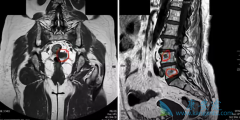

疼痛是晚期 宫颈癌症状 。癌瘤沿旁组织延伸,侵犯骨盆壁,压迫周围神经,临床表现为坐骨神经或一侧骶、髂部的持续性疼痛。肿瘤压迫或侵蚀输尿管,管道狭窄、阻塞导致肾盂积水,表现为一侧腰痛,甚至剧痛,进一步发展为肾功能衰竭,甚至尿毒症。淋巴系统 ...